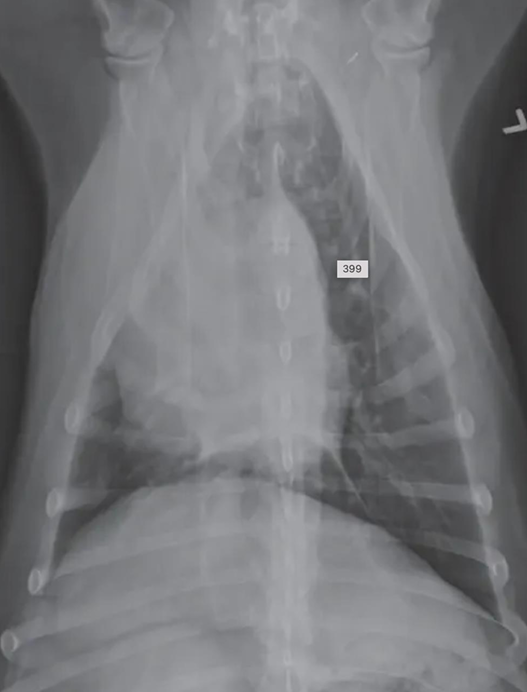

![]() | Mediastinum - abnormal shift - 여기서는 심장이 오른쪽으로 붙음 - 무기폐, 폐자름술, 폐종양일 때 발생 |